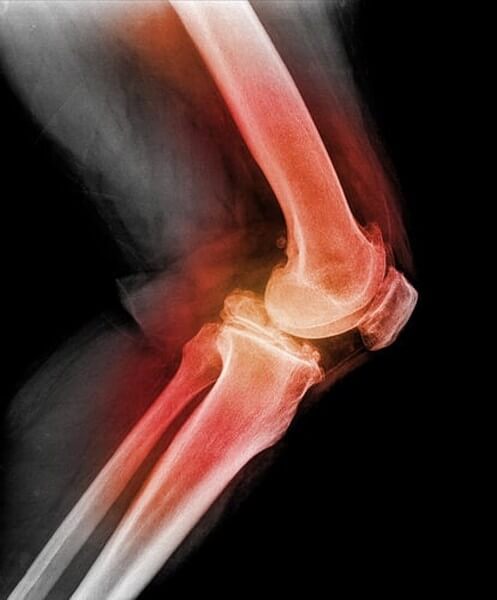

Rottura della rotula. Quando questo stress è traumatico, e di là di quanto l’osso in grado di sopportare, può verificarsi una rottura della rotula con conseguente frattura Rappresenta l’1% di tutte le fratture del corpo umano, ed più frequente negli uomini La frattura di rotula può essere di varia entità e danno. La frattura della rotula è una problematica che colpisce il ginocchio ed è riscontrata frequentemente in ambito ortopedico, rappresentando circa il 60% delle fratture che interessano il ginocchio Queste sono delle lesioni estremamente invalidanti per il soggetto che le subisce poiché compromettono il meccanismo di estensione dell’arto inferiore, funzione indispensabile in tutti i. La fractura de rótula, también llamada fractura patelar, es la rotura o pérdida de continuidad ósea del hueso rotulianoAl encontrarse este hueso en la parte anterior de la rodilla es más propenso al golpe La mayoría de estas fracturas ocurren como resultado de traumatismos por accidente de tránsito o caída.

• Fratture della rotula • Rottura di molte fibre • Dolore acuto • Arresto dello sforzo, zoppia • Recupero in 46 settimane La rottura • Rottura di molti fasci • Dolore acuto • Impotenza completa • Infossamento precoce • Recupero in più di 3 mesi. L’articolazione del ginocchio è composta da tre ossa femore, tibia e rotula Quest’ultima, a causa della sua collocazione, è quella che corre un maggior rischio di frattura in caso di trauma Un infortunio serio che può limitare se non impedire i movimenti Che caratteristiche ha la frattura della rotula e come si interviene in sua. Berkeley Electronic Press Selected Works.

La frattura della rotula è un evento che si verifica quasi esclusivamente in seguito a un trauma diretto Questo perché la rotula è la zona del ginocchio più esposta verso l’esterno Delle tre ossa che formano il ginocchio, che sono la tibia, il femore e la rotula, quest’ultima è facilmente e direttamente palpabile anche dai non espertiNelle cadute dalle scale l’impatto è sempre. Gentilissimo dottore, a mia moglie, a causa di una caduta, è stata riscontrata la frattura pluriframmentaria scomposta della rotula con diastasi fra i 2 frammenti di circa 3,2 centimetri, vorrei. Sintomi, con la rottura della cartilagine, e tali movimenti Precedenti infortuni al ginocchio come una distorsione o una lussazione della rotula con conseguente rottura di uno dei Artrosi ginocchio sintomi e terapie utili L artrosi al ginocchio pu essere trattata con diverse tipologie d intervento.

È la rottura della rotula e solitamente avviene per un trauma diretto tra la rotula e una superficie dura Le situazioni a cui può essere dovuta sono la caduta;. Le malattie che interessano la rotula variano, partendo dalla lussazione e arrivando alla rottura dei legamenti e i tendini collegati alla rotula In molti casi ricorrere al centramento della rotula con l’ausilio di un tutore può correggere o alleviare il problema, ma anche prevenirlo se necessario. Altrettanto raramente può verificarsi una frattura della rotula da stress associato ad un aumento del volume di salto Anche una lussazione può tuttavia comportare una frattura della rotula, in particolar modo se forzata Sintomi Il tipico sintomo in presenza di frattura della rotula è il dolore al livello del ginocchio.

Il test di sollevamento della gamba tesa può rivelare la rottura del meccanismo estensore, che include il tendine del quadricipite, la rotula e il tendine rotuleo Imaging e laboratori Una radiografia è spesso il primo test di imaging utilizzato, in quanto può mostrare se è presente una frattura, che è importante individuare o escludere. • Fratture della rotula • Rottura di molte fibre • Dolore acuto • Arresto dello sforzo, zoppia • Recupero in 46 settimane La rottura • Rottura di molti fasci • Dolore acuto • Impotenza completa • Infossamento precoce • Recupero in più di 3 mesi. Malattie della Rotula Le più note problematiche che possono interessare la rotula sono la lussazione (o dislocazione), la rottura del tendine rotuleo e la frattura LUSSAZIONE DELLA ROTULA La lussazione della rotula, o dislocazione patellare, è quando la rotula scivola fuori dalla sua normale posizione.

Anatomia della rotula La rotula o patella è un osso sesamoide corto, tozzo e massiccio a forma di castagna con la base superiore e l'apice inferiore Il suo margine superiore da inserzione al tendine del quadricipite femorale che si prolunga in un tendine robusto che a sua volta decorre dall'apice inferiore della rotula fino alla tuberosità. Il test di sollevamento della gamba tesa può rivelare la rottura del meccanismo estensore, che include il tendine del quadricipite, la rotula e il tendine rotuleo Imaging e laboratori Una radiografia è spesso il primo test di imaging utilizzato, in quanto può mostrare se è presente una frattura, che è importante individuare o escludere. A settembre sono caduta e rotta la rotula destra, operata e due trasfusioni un po’ anemica con beta talassemia Tra tre mesi dovrei rimuovere tutto e necessario?.

Fratture della rotula In caso di frattura della rotula si avranno dolore, impossibilità di piegare il ginocchio, ecchimosi Talvolta è imposibile ridurre o curare la frattura della rotula mediante l’applicazione d’una fasciatura elastica o di una ginocchiera gessata seguita dopo circa quindici giorni di massaggi. A settembre sono caduta e rotta la rotula destra, operata e due trasfusioni un po’ anemica con beta talassemia Tra tre mesi dovrei rimuovere tutto e necessario?. Leggi la voce ROTULA sul Dizionario della Salute ROTULA definizione, ultime notizie, immagini e video dal dizionario medico del Corriere della Sera.

Colpi di arti marziali finiti male;. La frattura della rotula provoca una grave limitazione del movimento del ginocchio perché il dolore si sente anche quando si cammina La rottura della patella rappresenta circa l’1% di tutte le fratture e oltre la metà di quelle del ginocchio I fattori che predispongono a questo tipo di frattura sono Osteoporosi;. Complicanze intervento?riprendere come prima ?.